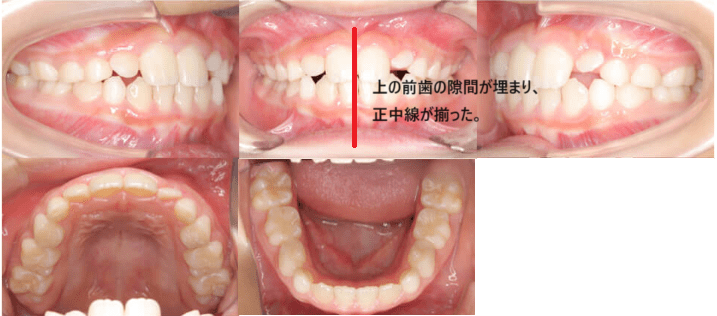

治療例①8歳11ヶ月

| 初診時年齢 | 8歳11ヶ月 |

| 主訴 | 歯が生える隙間がない |

| 診断 | 正中線の不一致を伴う不正咬合 |

| 抜歯の有無 | 非抜歯 |

| 治療内容 | 子供の歯が片側だけ早くに抜けてしまったため、大人の歯が生える隙間がなく、上下の歯並びの正中線がずれていた。 マウスピース型カスタムメイド矯正歯科装置(製品名インビザライン完成物薬機法外)を使用して、早くに抜けてしまった乳歯の分の隙間を回復し、上下の歯並びの正中線を揃えました。 |

| 治療期間 | 9カ月 通院回数7回 |

| リスク | 矯正歯科装置を付けた後しばらくは違和感、不快感、痛みなどが生じることがあります。 治療中は矯正歯科装置が歯の表面に付いているため食物が溜りやすく、また歯が磨きにくくなるため、むし歯や歯周病が生じるリスクが高まります。 歯を動かすことにより歯根が吸収して短くなることや歯肉がやせて下がることがあります。 |

| 費用 | 40万円 |

【治療前】

【治療後】